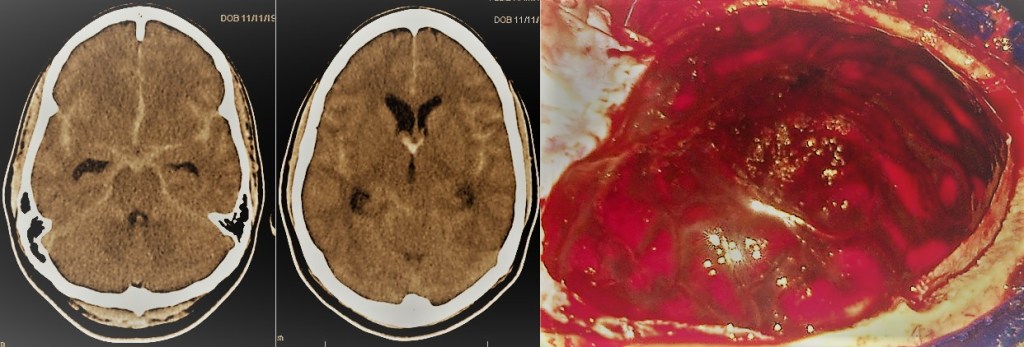

- Hematoma subdural agudo: Tiene lugar por debajo de la duramadre, la capa meníngea más superficial. Se encuentra por tanto en íntimo contacto con el cerebro. A diferencia de los anteriores, suelen presentarse en adultos generalmente mayores, lo que unido a su proximidad con el cerebro les confiere un peor pronóstico. En caso de alcanzar un volumen crítico o dar lugar a una alteración neurológica debe plantearse la evacuación quirúrgica.

- Contusión cerebral hemorrágica: Se trata de lesiones hemorrágicas dentro del cerebro como consecuencia de un traumatismo. Pueden aparecer o aumentar de tamaño de forma diferida, principalmente en las primeras 48-72 horas. En caso de alcanzar un volumen crítico o dar lugar a una alteración neurológica, debe valorarse la evacuación quirúrgica.